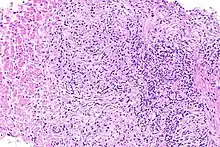

Prostatite é a inflamação da próstata. Pode ter origem bacteriana ou não-bacteriana e serem sintomáticas ou assintomáticas.